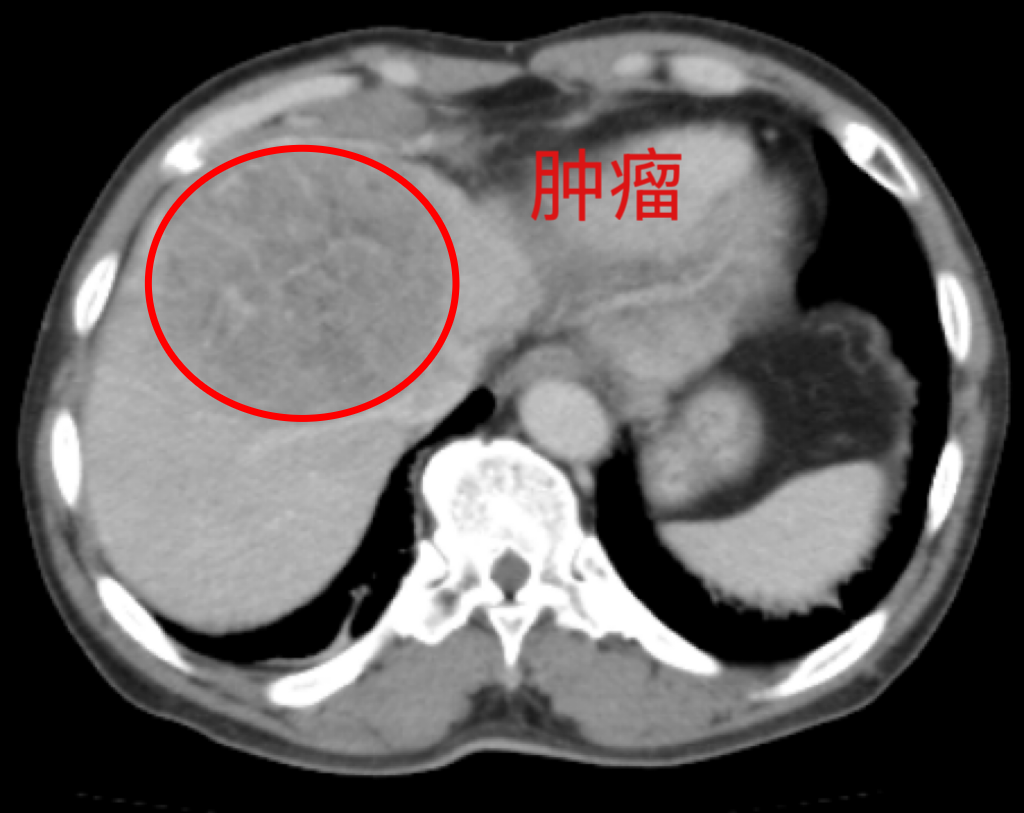

一个月前,63岁的李大爷因突发腹痛到当地医院就诊,CT检查结果显示肝脏占位性病变。经过进一步检查,被确诊为原发性肝癌。“肝癌”两个字如晴天霹雳,让李大爷一家人陷入恐慌,在朋友的介绍下转入贵州医科大学附属肿瘤医院肝胆外科。

(术前影像检查)

肝癌是严重威胁患者生命和健康的恶性肿瘤。外科手术是肝癌的主要治疗方式,原发性肝癌手术难度大、风险高,尤其对高龄患者而言,对手术团队的技术、围术期管理及术后康复均提出极高要求。接诊病人后,潘耀振教授团队高度重视,对其病情进行了全面且细致的评估,组织多学科会诊(MDT),结合影像学、肝功能评估及患者身体状况,分析手术可行性,最终制定了个体化的精准手术方案。